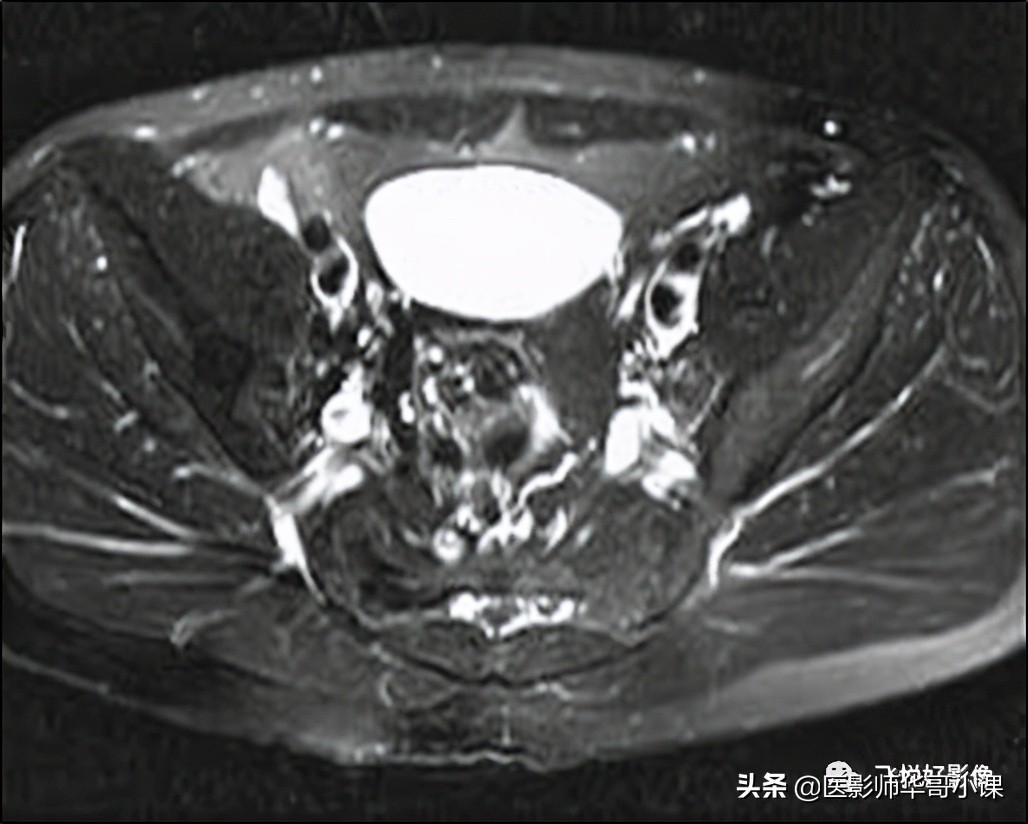

我们举一个常见例子,在做盆腔压脂序列时候,有时候会发现图像对角线部分会有一些信号不均匀及丢失等现象,这种伪影叫 四极电场伪影 。

该伪影产生的原因主要是人体在磁场内产生的涡流(内在固有效应),导致B1场分布不均匀,主要以横断面为主。

那么针对这种伪影,解决方法也很简单,换一种压脂方法。